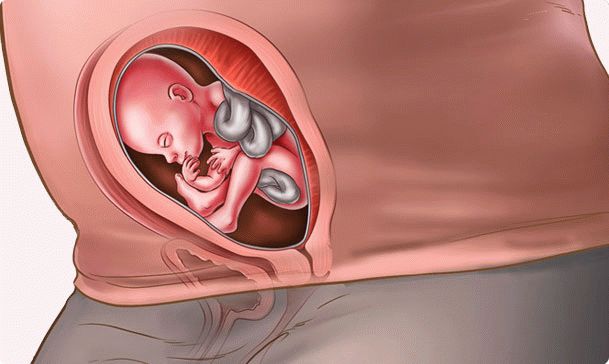

Maintenant, la tâche principale du fœtus est de grandir et de prendre du poids. L'enfant ressemble à un petit homme. Dans des proportions du corps, il ressemble déjà à un nouveau-né. Si votre bébé est destiné à naître avec des cheveux sur la tête, à cette époque, ils apparaissent. De minuscules sourcils et cils sont déjà là, mais ce ne sont probablement pas des poils, mais des peluches légères. Votre enfant s'entraîne constamment. Par les signaux du cerveau, le fœtus accomplit littéralement les mouvements dont il aura besoin en premier.

Cette semaine, le fruit atteindra une longueur de 18 cm et son poids atteindra environ trois cents grammes. N'oubliez pas: votre bébé entend déjà, alors parlez-lui.

Comment se situe le bébé dans l'utérus? Comme il veut. Ce n'est pas le moment de parler de la bonne ou de la mauvaise position du fœtus. Il y a suffisamment d'espace pour que les miettes tournent dans toutes les directions pendant quelques semaines de plus.